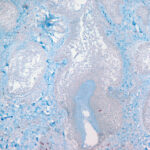

The mucin found in these six diseases represents an increase in the mucin that is normally present in the ground substance of the dermis. It consists of proteins bound to hyaluronic acid (hyaluronan), which is an acid mucopolysaccharide or glycosaminoglycan. As a result of the great water-binding capacity of hyaluronic acid, dermal mucin contains a considerable amount of water. This water is largely removed during the process of dehydration of the specimen; consequently, in routine sections, the mucin, because of its marked shrinkage, appears largely as threads and granules. |

The mucin present in the six types of mucinosis stains a light blue in sections stained with H&E. It also stains with colloidal iron. It is Alcian blue-positive at pH 2.5 but negative at pH 0.5 and shows metachromasia with toluidine blue at pH 7.0 and 4.0 but no metachromasia below pH 2.0 . It is PAS negative (indicating the absence of neutral mucopolysaccharides) and aldehyde fuchsin negative (indicating the absence of sulfated acid mucopolysaccharides). The mucin is completely removed on incubation of histologic sections with testicular hyaluronidase for 1 hour at 37″C . |